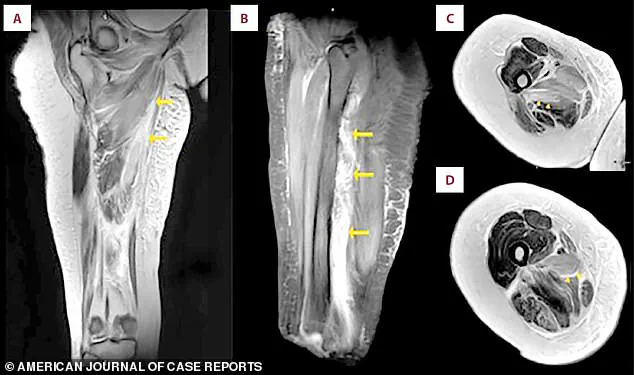

An MRI scan of the patient's right thigh revealed widespread muscle swelling.

The images, marked with arrows, pinpointed this fluid buildup in the inner thigh muscles (the adductor group) and, in a different view, showed similar swelling affecting the muscles at the back of the thigh.

These images were not just diagnostic tools; they were visual narratives of a body in distress, a testament to the invisible battles fought within the flesh and bone.